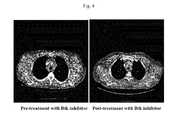

FIG. 4 depicts LN response in patient suffering from CLL. Left panel depicts LN prior to treatment with an irreversible Btk inhibitor and Right panel depicts LN post-treatment with an irreversible Btk inhibitor.